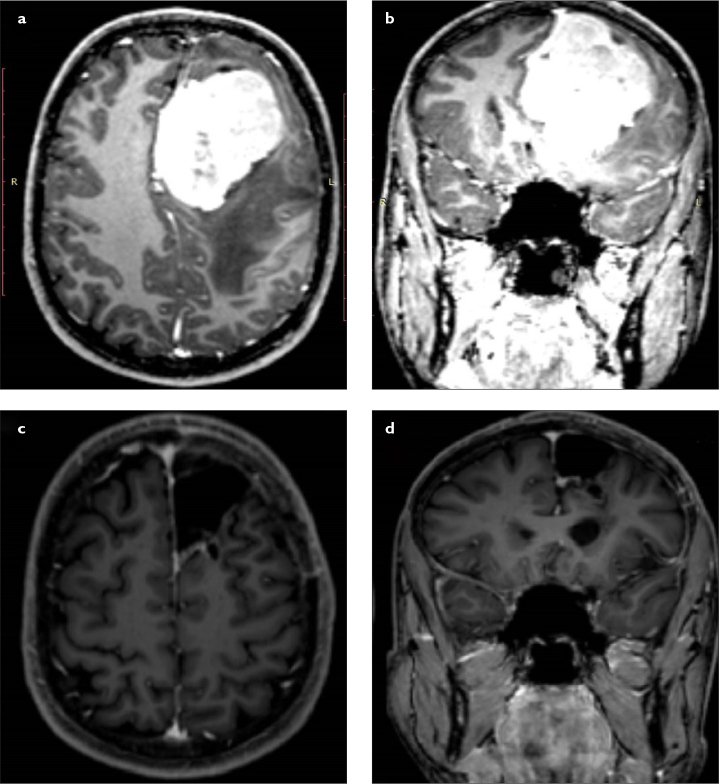

Objective: Giant intracranial meningiomas are a challenge for neurosurgeons because of their size and location in the cranium. Difficult tumor dissection and encasement of important neurovascular structures make them a horrible nightmare. The aims of this study are to present our giant intracranial meningioma series and to compare our experience using advanced surgical technology with the current literature.

Materials and methods: The data of patients with the diagnosis of giant intracranial meningioma between 2014 and 2020 who underwent surgical treatment were retrospectively reviewed. The demographic, radiological, and surgical characteristics of patients were documented. The size and location of tumors as well as surgical technique were analyzed in detail.

Results: A total of 61 patients with intracranial meningioma underwent surgical treatment over a 7-year period, and 10 (16.4%) tumors were larger than 5 cm in diameter, which were classified as giant meningioma. Seven patients were male and 3 were female, with a mean age of 64.9 years. Four tumors were located at the skull base. Histological diagnosis was meningioma World Health Organization grade I in 7 patients and grade II in 3 patients. Simpson grade 1 resection was achieved in 6 patients and grade 2 resection in 4 patients. No mortality was observed.

Conclusion: Careful surgical planning should be made for giant intracranial meningiomas. Their location, adjacent neurovascular structures, and vascular supply affect the resection level of these giant tumors. Simpson grade 1 resection is seldom possible for skull base meningiomas.